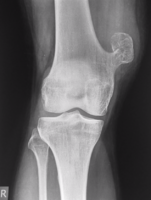

Medical imaging usually shows a well-defined wide-based bony growth on the surface of bone.[5] It can be pedunculated and irregular, giving it a "bizarre" appearance, and is not connected to underlying bone.[2]